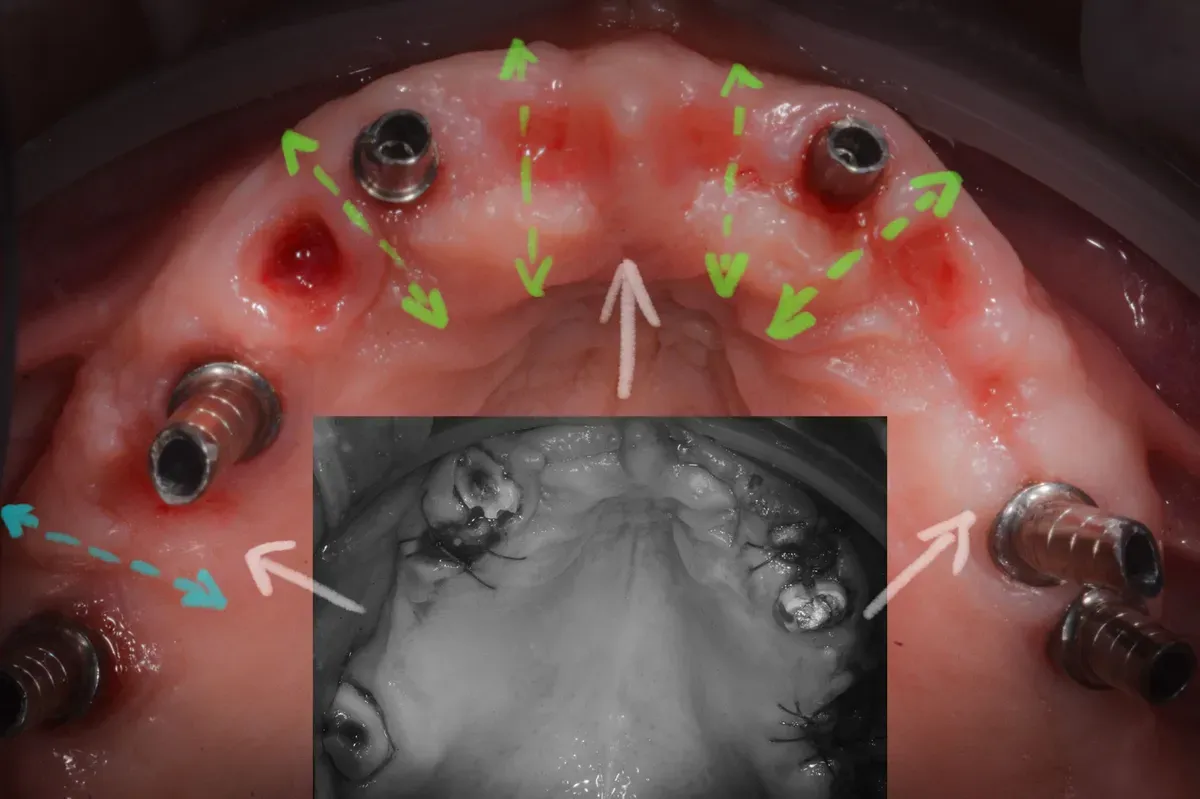

Il confronto tra le immagini cliniche prima e dopo il trattamento (vedi sotto) è impressionante e non lascia spazio a dubbi sull’efficacia delle tecniche di espansione osteo-mucosa.

L’aumento delle dimensioni effetto della rigenerazione

Le due immagini sembrano appartenere a due persone diverse: la dimensione trasversale e la cresta alveolare anteriore sono entrambe notevolmente aumentate, suggerendo una significativa variazione anatomica.

Inoltre, è impressionante notare che tutto questo aumento è stato ottenuto senza alcun tipo di innesto, il che sottolinea la capacità naturale del corpo di modificarsi e crescere in risposta agli stimoli chirurgici della guarigione per seconda intenzione.

Il controllo a distanza di anni

Al controllo radiografico, sette anni più tardi, gli impianti sono in ottima salute e perfettamente integrati (vedi immagini seguenti).